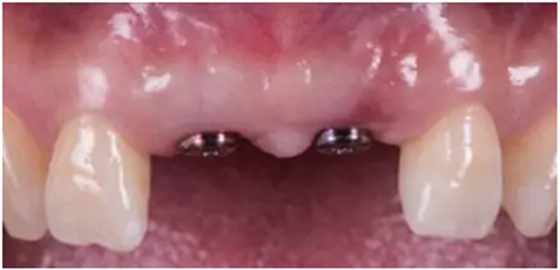

愈合基臺(tái)連接2周后

種植過(guò)渡義齒完成(螺絲固位)

種植過(guò)渡義齒試戴,調(diào)整唇側(cè)凸度,切端位置

患者剛戴入過(guò)渡義齒時(shí),發(fā)現(xiàn)牙齦泛白,范圍不超過(guò)鄰牙終點(diǎn)。若患者休息10分鐘后,牙齦顏色恢復(fù)正常,則說(shuō)明穿齦輪廓設(shè)計(jì)合理。

過(guò)渡義齒制作完成及試戴

過(guò)渡義齒佩戴3個(gè)月后